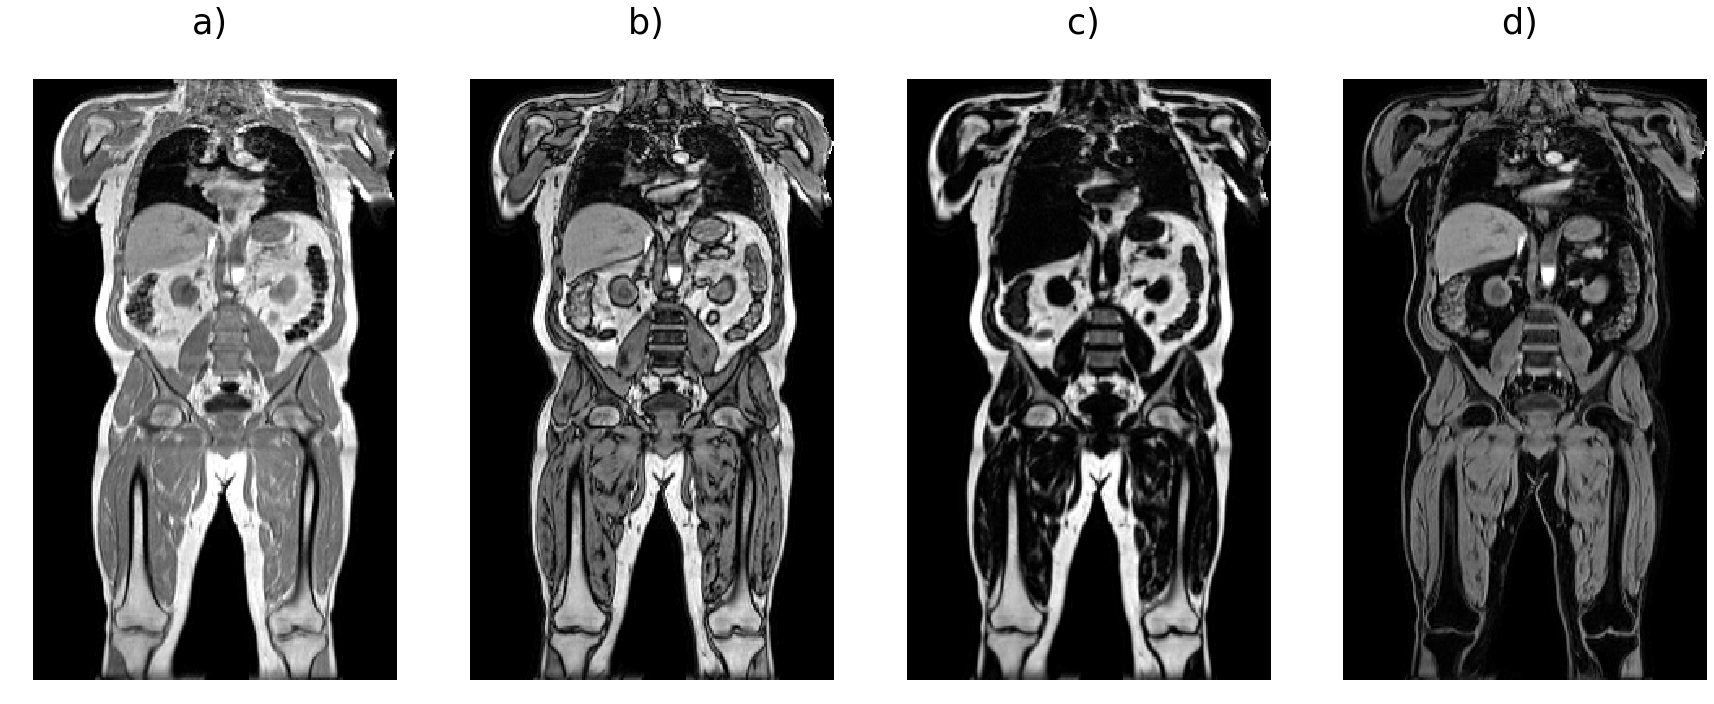

For the training data, fat-water separation was performed by the scanner reconstruction software on each Dixon series as provided by the UK Biobank. We performed minor preprocessing to assemble the six series into a single volume for each channel [6] (Fig. 1 a-d). Briefly, the six series were resampled to the same resolution (), bias-field correction [40] was performed on the in-phase volume and the estimated bias field applied to the other channels for each series, resulting in a final volume of size . Bias-field correction was performed a second time on the blended in-phase volume and the estimated bias field was applied to the other channels. Estimating the bias-field is a particularly computationally expensive step, the entire process takes approximately 20 minutes per scan. We selected 1,027 participants as swap-free ground truth data for our experiments, where visual inspection of the fat and water channels was performed for each participant to ensure no substantial swaps were present. The participants were chosen to cover a broad range of age, gender and body mass index values. During the process of quality control, we also identified more than 70 participants with at least one fat-water swap in the original fat and water channels. We used those scans to verify swap correction by visual inspection. When developing the neural network model we used the and channels as our input data and the and channels as the training labels.

There are indeed a variety of more complex fat-water swaps in the UK Biobank Dixon MRI datasets, including partial swaps that cover only a fraction of the volume or swaps related to the multiple (six) series acquired in the UK Biobank abdominal protocol. For example, the top of the liver may be swapped when it appears in the second series and is isolated from all other tissue by the lungs (Fig. 1 e-f), or one of the abdominal muscles may be swapped when isolated from all other tissue by internal fat. Localised fat-water swaps may also occur due to field inhomogeneities at the boundary of the field of view (Fig. 1 k-l). Swaps occur more frequently in subjects of extreme sizes, therefore not being able to quantify or even completely discarding these subjects may introduce bias in population studies. The UK Biobank is currently acquiring images for 100,000 participants, and plans to scan as many of them as possible for a second time as well as performing a separate COVID-19 study. This means that substantially more than 100,000 scans will be performed, thus we estimate that the images from close to 10,000 participants could be affected. It is essential that we develop methodologies that will ensure minimal data waste and that all analyses resulting from this impressive collection will reach their full potential.